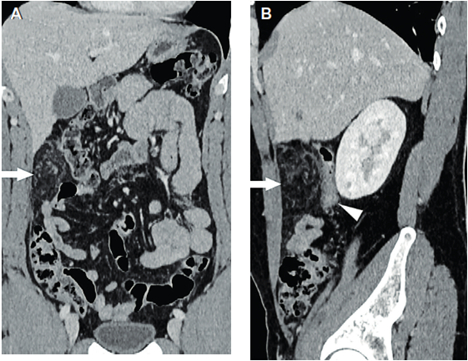

Ante la persistencia del dolor se decidió complementar los estudios con tomografía computarizada de abdomen con y sin contraste intravenoso (Figuras 1 y 2) donde se aprecia infarto del omento, para lo que se inicia tratamiento médico conservador. Luego de 24 horas aumenta el dolor abdominal, por lo que se realiza laparoscopia exploradora. En el intraoperatorio, se confirma necrosis del sector superior derecho del epiplón mayor; se realiza la resección con ligasure® (Figura 3). Tuvo buena evolución posoperatoria, dando de alta a las 48 horas. La anatomía patológica confirmó el diagnóstico de infarto omental.

Figura 2. Rreconstrucción en plano coronal (A) y plano sagital (B). Alteración bien circunscripta en el epiplón mayor a nivel de flanco derecho (flechas), que determina ligero efecto de masa sobre el colon ascendente (punta de flecha).